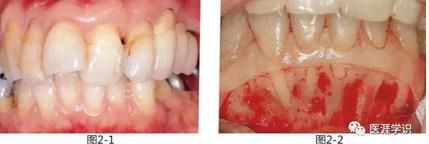

圖2-1,2 為了采集自體骨而將下頜骨頦部進(jìn)行剝離,發(fā)現(xiàn)下頜前牙部無唇側(cè)骨壁。